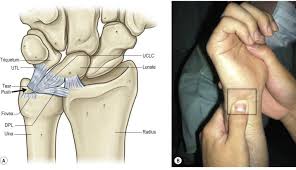

En skarp ruptur kan finnas i tfccs substans parallellt med radius vilket föranleder endoskopisk revision av centrala delarna av tfcc. Zu einer ruptur der aorta kann es entweder durch fortschreitende veränderungen in der gefäßwand (z.b. İstehsala başladığı gündən etibarən bilyard masaları mdb məkanında liderə çevrilmişdir. Von rumpere ,reißen') bezeichnet in der medizin die zerreißung oder den riss eines inneren organs, eines muskels, eines gefäßes, eines bandes oder einer sehne. Aortic rupture is a rare, extremely dangerous condition. Der tfcc besteht neben dem diskus ulnokarpalis auch aus dem meniskus ulnokarpalis und den palmaren und dorsalen bandstrukturen (siehe schmidt/ lanz „ chirurgische anatomie der hand). Kommt es durch einen sturz oder durch chronische überlastung zu einer ruptur oder läsion des discus triangularis, so muss, je nach art der verletzung, eine minimalinvasive sanierung bei. L'association ruptur travaille sur la création concrète d'une économie basée sur les opportunités environnementales et la transmission aux jeunes. Aortic rupture is the rupture or breakage of the aorta, the largest artery in the body. (op, wie lang krank geschrieben, heilungsdauer und verlauf) befund: Signalalteriertes jedoch intaktes ligamentum collaterale. Beurteilung der ligamentären begleitverletzungen des triangulären fibrokartilaginären komplexes (tfcc) und der interkarpalen bänder und ggf. Sehnen stellen die verbindung zwischen muskeln und knochen dar.

Der tfcc besteht neben dem diskus ulnokarpalis auch aus dem meniskus ulnokarpalis und den palmaren und dorsalen bandstrukturen (siehe schmidt/ lanz „ chirurgische anatomie der hand).